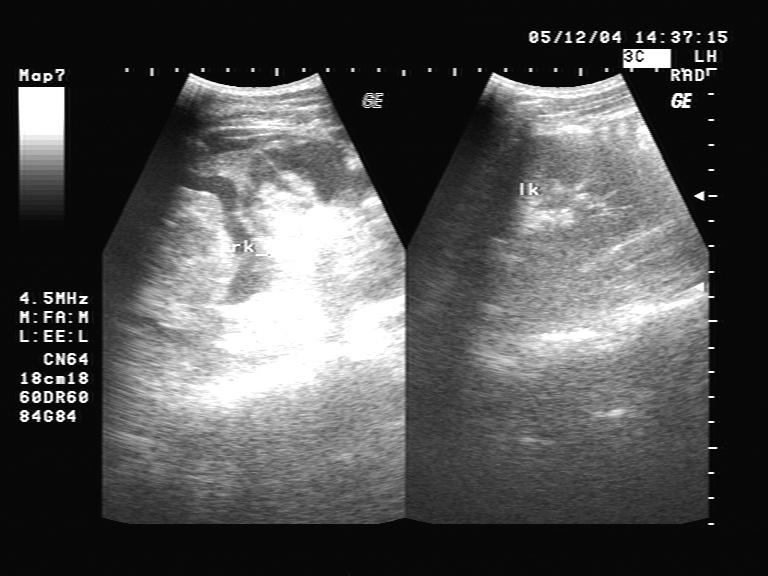

右肾挫裂伤 - 超声医学讨论版 - 爱爱医医学论坛

图片尺寸465x366